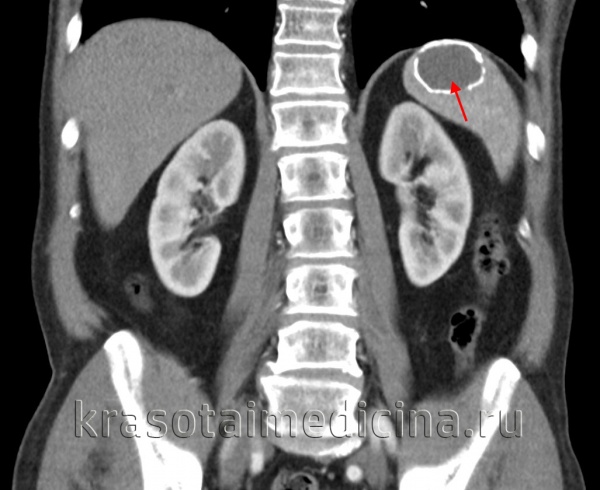

(Слева) На корональной КТ с контрастным усилением у молодой девушки визуализируется большая киста в селезенке, выглядящая простой. Пациентка предъявляла жалобы на боль и раннее насыщение, ей было выполнена операция — иссечение стенки кисты.

(Справа) Макропрепарат удаленной (у этого же пациента) селезенки: кальцинированная стенка кисты, состоящая из фиброзной ткани. Эта киста является приобретенной и возникла, скорее всего, в результате травмы или инфаркта. (Слева) На корональной КТ с контрастным усилением у молодой девушки визуализируется большая киста в селезенке, выглядящая простой. Пациентка предъявляла жалобы на боль и раннее насыщение, ей было выполнена операция — иссечение стенки кисты.